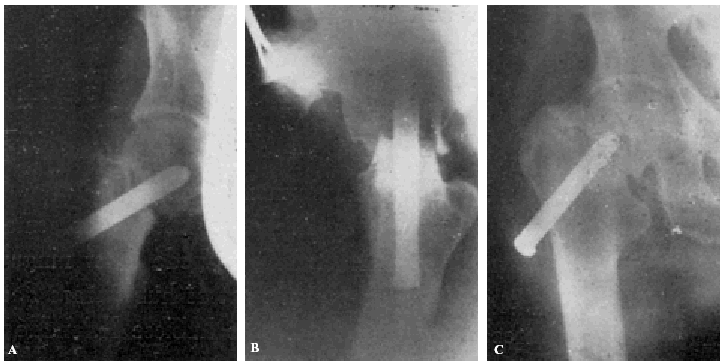

Con buena técnica, todos los resultados son favorables, a pesar de que al cabo de algunos años exista un grado más o menos acentuado de artrosis (véanse la observación núm. 4, fig. 7., A y B, y la observación núm. 9, fig., 8. A, B y C), que corresponden a los dos enfermos que hace más tiempo que están operados, y que en la actualidad aún viven.

Figura 7. A: obs. núm. 4. Enfermo de sesenta y cuatro años, operado en noviembre de 1935. La situación del clavo puede aceptarse como buena (ligeramente craneal). B: obs. núm. 4. Radiografía del mismo enfermo de las dos figuras anteriores, practicada en la actualidad (julio de 1943). Artrosis manifiesta. La cabeza del fémur tiende a aplastarse. Deambulación perfecta.

Figura 8. A: obs. núm. 9. Enferma de cuarenta y cinco años, operada en enero de 1937. El clavo procedía del cadáver de la observación mencionada como fracaso número I, y presentaba unos ligeros depósitos de herrumbre. La situación del clavo es buena. B: obs. núm. 9. El mismo caso de la figura anterior. En proyección lateral también es perfecta la situación del clavo. Éste tuvo que ser extraído a los siete meses de intervenida la fractura, a causa de una persistente supuración. C: obs. núm. 9. Radiografía del caso de las dos figuras anteriores, practicada en julio de 1943. Artrosis muy ligera. El cuello del fémur parece muy estrechado, pero esta deformidad también puede apreciarse en la figura B. Deambulación perfecta.

Muchos fracasos de Böhler se deben a haber cargado precozmente la extremidad. La figura 15, A y B8, corresponde a un fracturado operado por Böhler. El clavo está bien colocado en las dos proyecciones, aunque es poco profundo y ligeramente ventral en lugar de dorsal. A los dos meses, cuando el enfermo andaba perfectamente bien, nota el enfermo bruscamente dolores y se comprueba a la exploración radiográfica que el clavo se había salido de la cabeza del fémur (fig. 15, C y D). Dice Böhler, referente a este caso: «Este desprendimiento no habría ocurrido si el clavo se hubiera colocado algo más caudal y más dorsal respecto a la línea media del cuello y de la cabeza y, a la vez, hubiese penetrado lo suficiente en ésta». Y añadimos nosotros: a pesar de que la situación del clavo no era idealmente perfecta en este caso, la culpa del fracaso reside fundamentalmente en la carga precoz del miembro fracturado. Si observamos la figura 16, A y B (observación núm. 23), aunque en proyección anteroposterior, la situación del clavo puede considerarse perfecta; en proyección lateral, está en situación mucho más ventral que la observación anterior de Böhler, y sin embargo la enferma, operada en mayo de 1941, anda en la actualidad, a pesar de sus setenta y ocho años, sin la ayuda de ningún bastón y sin presentar ninguna molestia (fig. 16 C). La situación del clavo en este caso es muy semejante a la de la enferma citada anteriormente, que falleció al extraerle el clavo intolerante (supuración de la herida, sin síntomas generales de infección) (fig. 17 A y B; obs. núm. 18), por lo que todo hace suponer que, en caso de no haberse presentado el desenlace fatal, el resultado funcional hubiera sido bueno.

Figura 15. A: comprobación roentgenológica después de colocar el clavo e impactar los fragmentos. La diástasis entre éstos ha desaparecido. El clavo está en el centro del cuello y de la cabeza, pero no lo suficiente profundo, puesto que su punto dista 13 mm. de la superficie de la cabeza, en vez de 3 a 6 mm. B: en la proyección lateral, el clavo está colocado algo hacia delante, es decir, demasiado ventral, en la cabeza del fémur. (De Böhler Jeschke.)

Figura 15. C y D: al principio andaba perfectamente, pero de pronto se le presentaron dolores, y en la roentgenografía se vio que el clavo se había salido de la cabeza del fémur y los fragmentos habían vuelto a desviarse a la posición que tenían antes de la reducción. Este desprendimiento no habría ocurrido si el clavo se hubiera colocado algo más caudal y más dorsal respecto a la línea media del cuello y de la cabeza, y, a la vez, hubiese penetrado lo suficiente en ésta. (De BöhlerJeschke.)

Figura 16. A: obs. núm. 23. La situación del clavo en esta proyección es buena. B: obs. núm. 23. El mismo caso de la figura anterior, en proyección lateral. La situación del clavo es excesivamente ventral. C: Obs. núm. 23. El mismo caso de la figura anterior, en la actualidad. A pesar de la artro-sis existente, la enferma no presenta la más mínima molestia ni se halla limitada la movilidad articular.

Figura 17. obs. núm. 18. La fractura está enclavada en valgus. El clavo está bien colocado, aunque es algo corto. B: obs. núm. 18. El mismo caso de la figura anterior, en posición lateral. El clavo, algo corto, está colocado en la misma posición defectuosa que el caso de la figura 16, B.